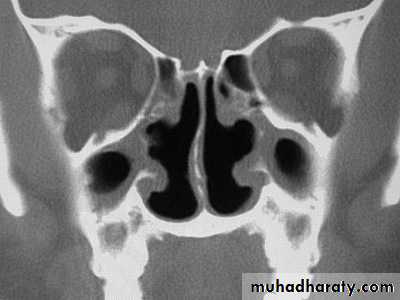

• (c)Atrophic rhinitis

• Definition• A chronic inflammation of the nasal mucosa . in which its various constituents undergo atrophy as a result of per arterial fibrosis and endarteritis of the terminal arterioles .

• Pathology

• Degeneration of the ciliated epithelium and seromucinous glands causes the formation of thick adherent crusts in the nose theses become secondarily infected with saprophytic organism the bony structures of the turbinate atrophy and the airway is widened . the sinuses may be small due to arrested pneumatization but are often normal there appear to be tendency to spontaneous recovery in later life in some cases• Clinical feature

• The conditions now seldom seen is bilateral and more common in female it appear about puberty• 1.foul stench not noticed by the patient who is anosmic

• 2.epistaxis may follow separation of the crust

• 3. sensation of obstruction despite the unduly wide airway